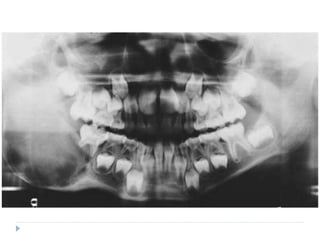

RADIOGRAPHIC FEATURES

 Radiolucent destruction of the bone with ragged and

ill-defined margins

 Radiolucency may begin as several small areas

which eventually enlarge and coalesce

 Patchy loss of the lamina dura is one of the early

sign of Burkitt’s lymphoma